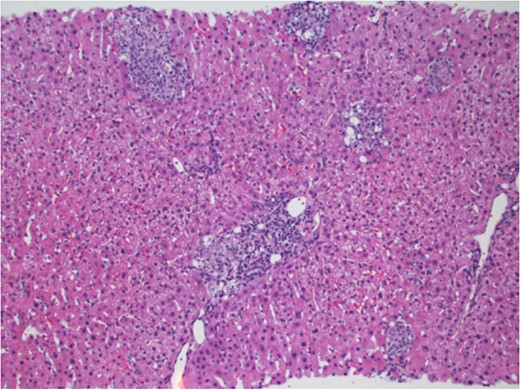

In March 2017, the patient presented with 2 weeks of generalized body aches, fevers, mild congestion and dysuria. His transaminases worsened—AST 360 U/L, ALT 387 U/L. Blood, urine and sputum cultures grew no organisms and the patient had a normal chest radiograph and abdominal ultrasound. CT sinus, obtained to rule out sinusitis, remarked on few mucous retention cysts of the maxillary sinuses, but was otherwise negative for any other pathology. However, further interrogation found that the patient had significant opportunistic infection exposure risk; the patient was a butcher at a local grocery store, and owned a new rabbit, several parakeets and four dogs. A repeat liver biopsy was performed, and this time, was found to have predominantly lobular, and occasionally portal, epithelioid granulomas (Fig. 1) with intracellular yeast-like elements (Fig. 2). These were described as narrow-based budding yeasts favoring histoplasma (Fig. 3). No portal based features of acute rejection were noted and bile ducts were preserved in the majority of portal tracts. Urine histoplasma antigen testing corroborated the histology finding—the patient had progressive disseminated histoplasmosis manifested as granulomatous hepatitis. He completed an 11-day course of liposomal amphotericin B and will continue itraconazole therapy for a year. His immunosuppression regimen was significantly decreased and mycophenolate was stopped. The most recent liver biopsy in May 2017 revealed a persistent—though significantly decreased—lobular inflammation, microgranulomas and budding yeast elements. His transaminases remain elevated at AST 265 U/L and ALT 259 U/L. He will continue close follow up to ensure further improvement on current therapy and resolution of Histoplasmosis.

Liver parenchyma with multiple discrete portal and lobular granulomas. Hematoxylin and Eosin stain ×100.